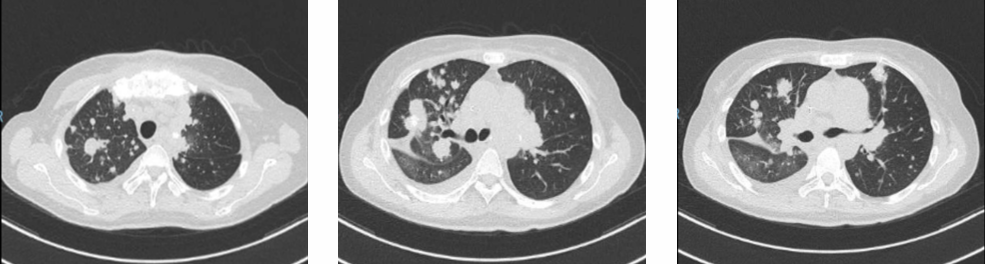

一线治疗影像评估:

2017年1月

2017年9月

影像评估:

2018年4月

2018年7月

2019年4月